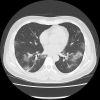

Pneumonia without Respiratory Symptoms